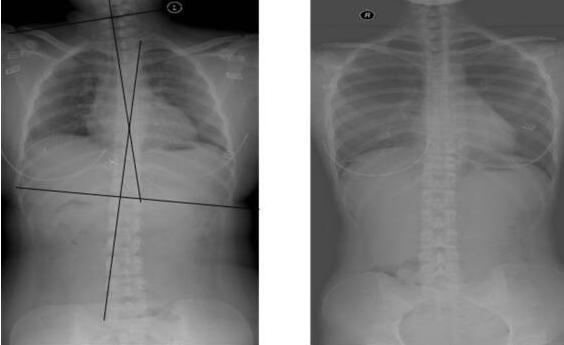

特别是脊椎变形的问题,很多家长都经历过,如果没有及时发现就医,可能会影响孩子一辈子。一、因为一个动作,孩子的脊椎轻微变形朋友小雨前几天讲述了一件心惊胆战的事情,在宝妈群引起一大批人讨论。她的孩子已经有九个月大了,孩子会站以后她就经常把孩子放在学步车里,让孩子能自己活动。孩子经常自己在学步车里歪着头走路,小雨纠正了好几次也没有成功,时间久了她发现孩子的腿部也有一些变形了。

家人觉得孩子是不是有些O型腿了,赶紧带着孩子去找医生,听说孩子九个月就开始学走路了,而且还经常在学步车里自由活动,医生无奈的解释,孩子太早学走路,非常容易让脊椎变形,而且腿型也会变成O型腿。一般来说孩子是6个月会坐,8个月会爬,9-11个月会扶着东西站立,初步开始学习走路。家长可以让孩子扶着东西走路,或者是牵着孩子走,放在学步车里也是有风险的。二、关于脊柱变形有这样几个问题1. 为什么婴幼儿的脊椎容易变形?胎儿的脊椎都是呈现C的形状,这和成年人的4个曲线完全不一样。经过一段时间的发育,孩子出生以后脊椎就像是一条直线,这个时候如果经常采用不合适的姿势抱孩子,很可能就让孩子的脊椎变形了。

因为生长形态不一样,所以新生儿需要注意保护脊椎,以免变形影响今后生活。2. 哪些症状判断孩子脊椎有问题?如果孩子总是偏头,或者走路有些长短脚的感觉,或者摸着孩子的记住明显有弯曲弧度,那就及时去医院察看。轻微的弯曲,是可以矫正过来的。3. 脊椎变形有什么危害?孩子的脊椎如果弯曲定型,没有矫正过来的话,孩子的内脏可能都会受到影响。外貌体型都会出现问题,高低肩、长短脚、驼背等等,在外貌竞争是没有任何优势的。而且脊椎变形,对人体的受力也产生影响,严重的话可能要手术矫正。